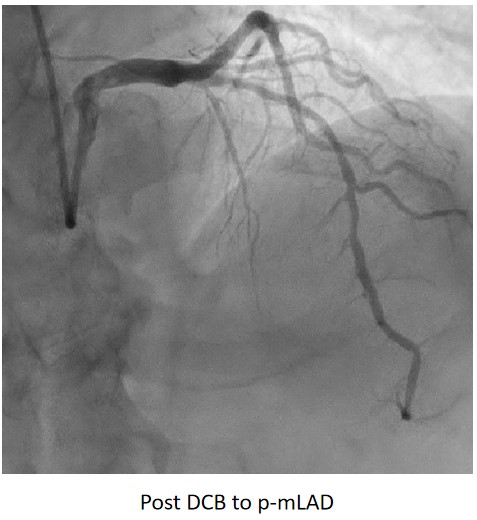

Urgent coronary angiography showed smooth LMCA with severe 3-vessel involvement. There was diffuse LAD lesion with critical stenosis at proximal-to-mid segment. Mid-segment of LCx was 90% stenosed while RCA was heavily calcified with critical stenosis at its mid segment. Our strategy will be complete revascularisation by employing DCB-only strategy.

Complete revascularisation was achieved with 2-staged procedures. Up-front plaque modification with rotational atherectomy/IVL with IVUS was planned but limited by patient¡¯s cost constraint. Vascular access obtained with transradial puncture with 6 Fr sheath. Guiding catheter (GC) Judkins Right 4.0 (Cordis, USA) 6 Fr was used to engage right coronary ostium. Runthrough Floppy (Terumo, Japan) wire was wired down RCA. Pre-dilatation balloons were unable to cross the heavily calcified mRCA lesion. Next, GC was changed to Amplatz Left 1.0 (Cordis, USA) for better support and proceeded for further lesion preparation with cutting balloon Wolverine (Boston Scientific, USA) 3.5 x 10 mm and DCB Prevail (Medtronic, USA) 3.0 x 20 mm was deployed. We scheduled him for staged PCI to the left coronaries in 2 weeks time via transradial approach with 6 Fr sheath. GC XB LAD 3.5 (Cordis, USA) 6 Fr was used to engage left coronary ostium. Runthrough Floppy was wired down LCx. Mid-distal LCx was prepared with Pantera Pro (Biotronik, Germany) 2.5 x 15 mm and DCB Pantera Lux (Biotronik ,Germany) 3.0 x 15 mm was deployed. Finally, we wired down LAD with Runthrough Floppy. Mid-distal LAD lesion was prepared with Pantera Pro 2.5 x 15 mm and DCB Pantera Lux 3.0 x 30 mm was deployed. Proximal LAD lesion, which was calcified, was further prepared with Wolverine 2.5 x 10 mm before DCB Pantera Lux 3.5 x 30 mm was deployed. Final post-PCI results were acceptable, achieving complete revascularisation for him.